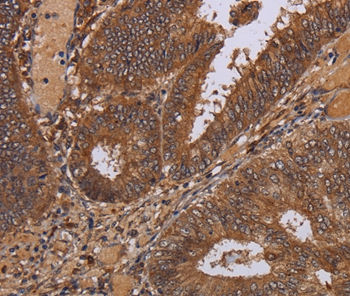

Immunohistochemical analysis of paraffin-embedded Human colon cancer tissue using #36600 at dilution 1/30.